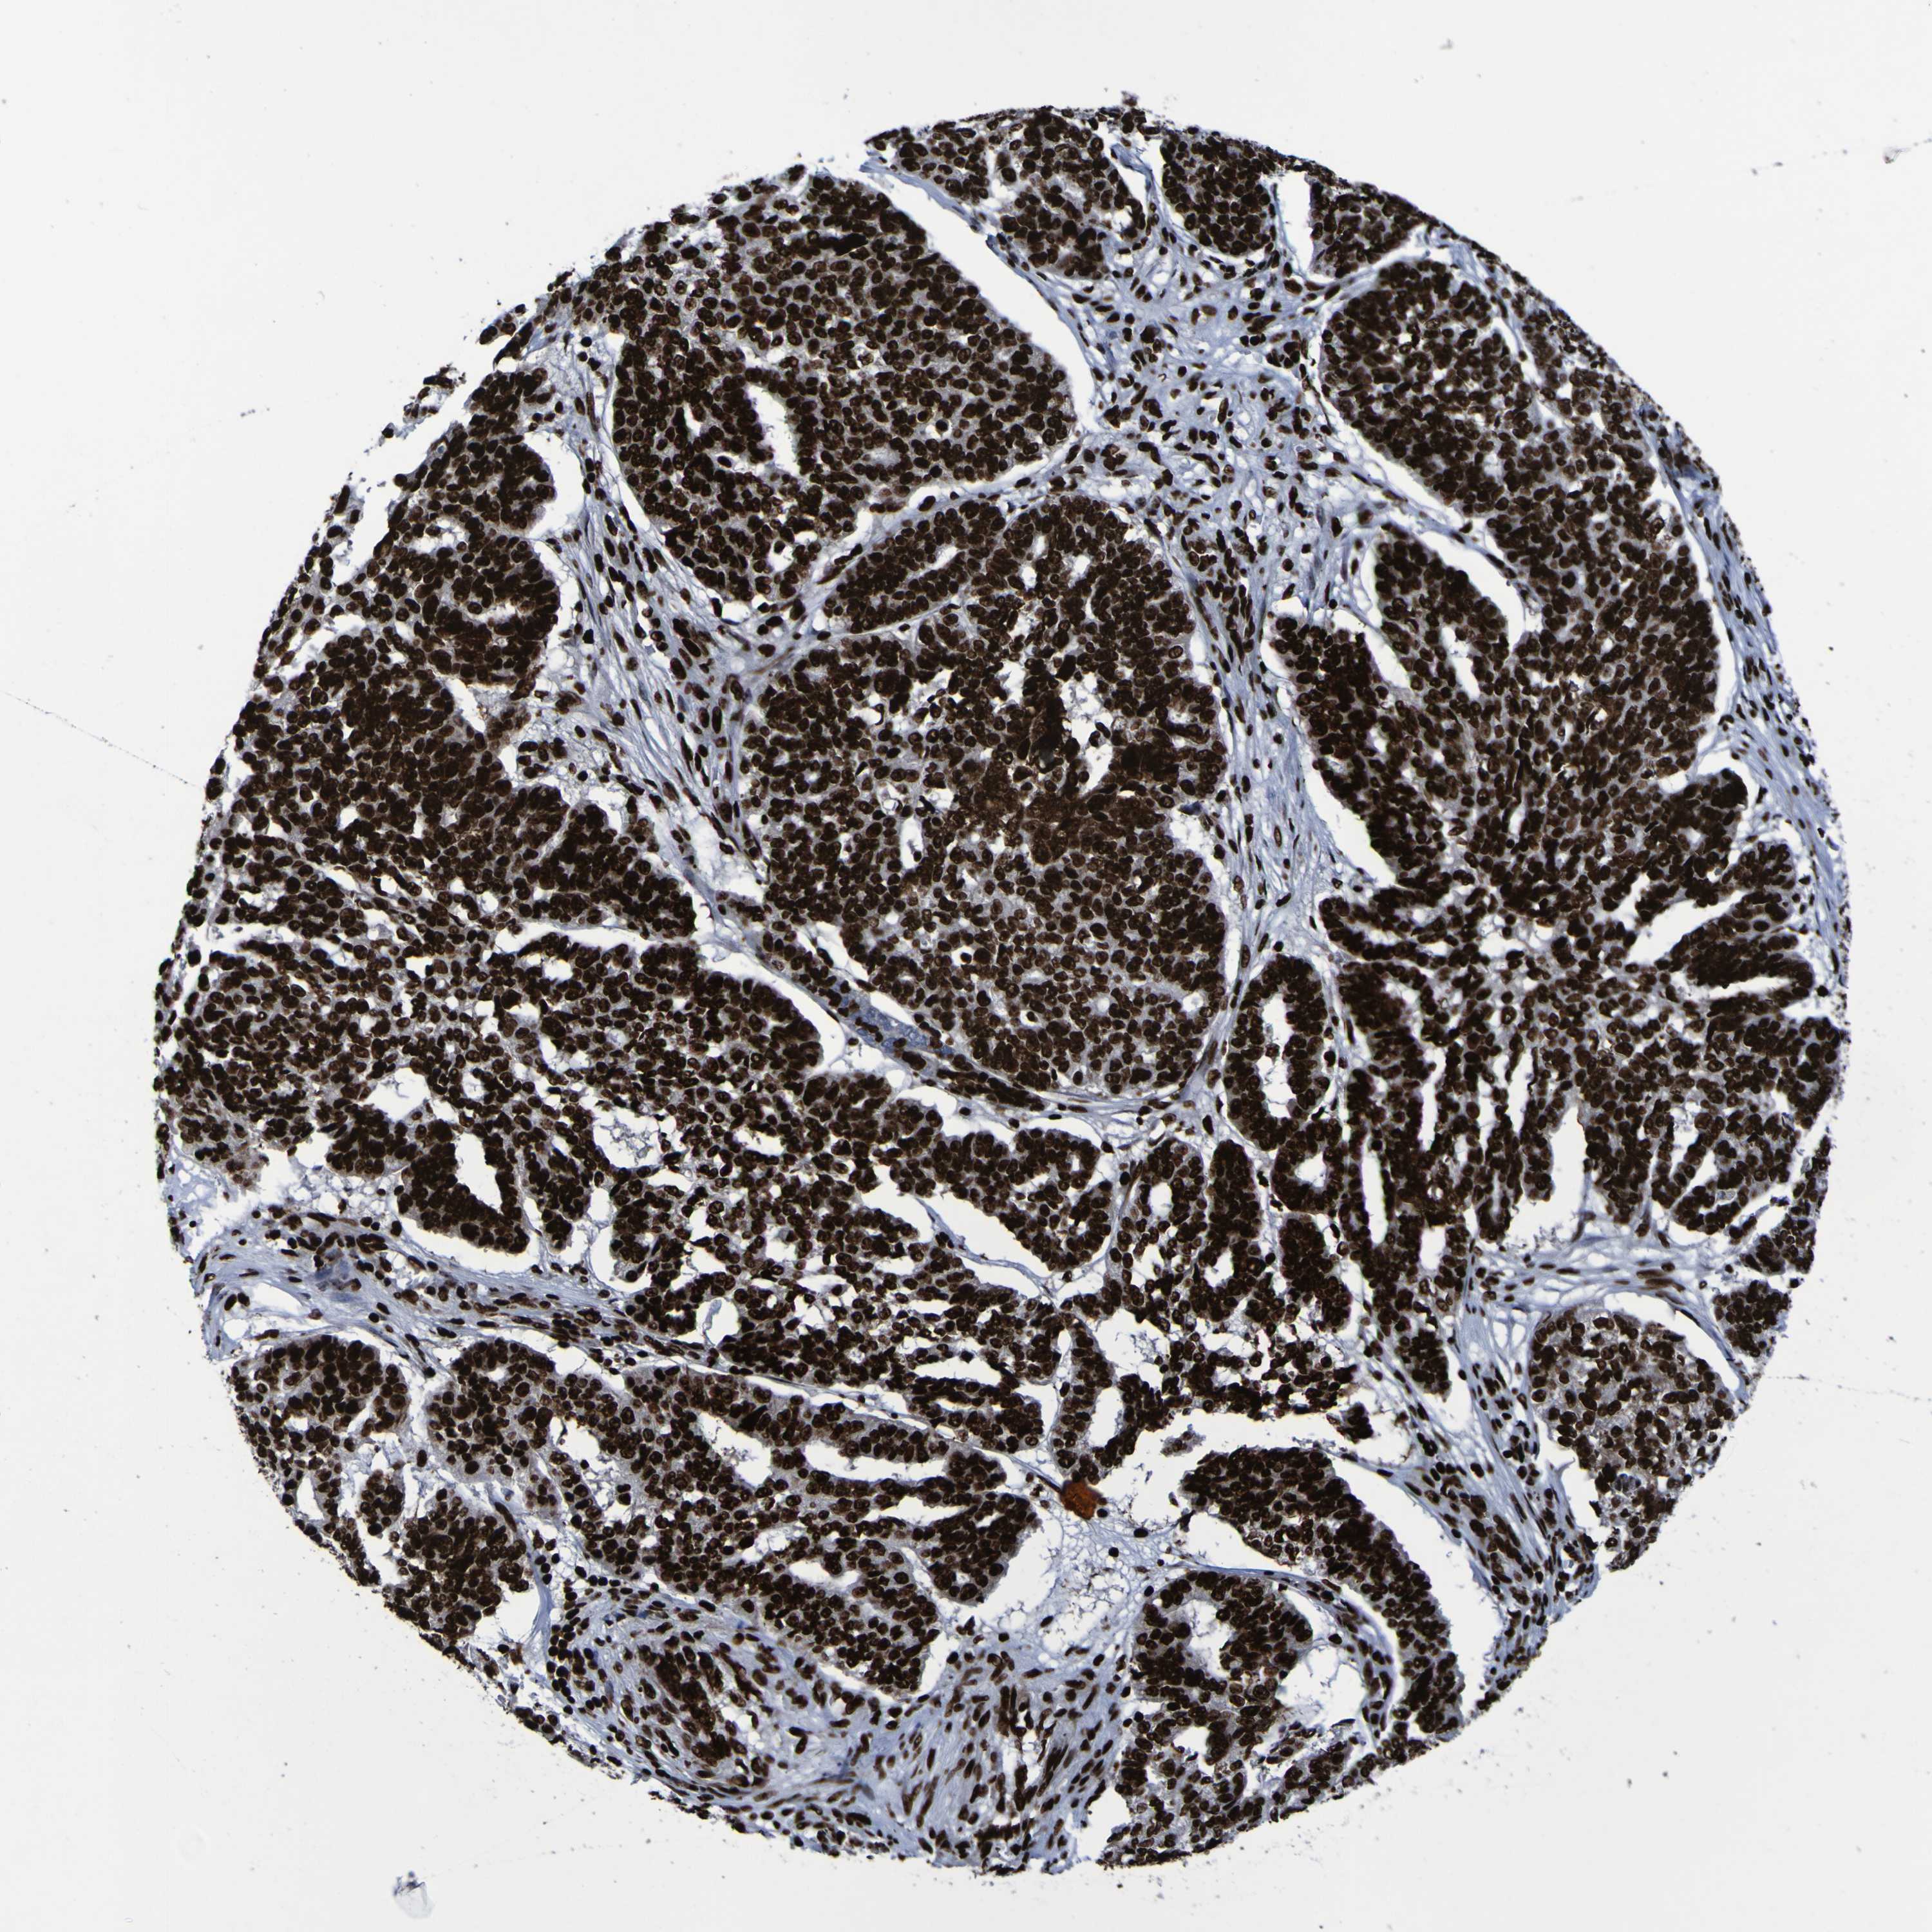

OVARIAN CANCER - Protein expressioni

A mouse-over function shows sample information and annotation data. Click on an image to view it in a full screen mode. Samples can be filtered based on level of antibody staining by selecting one or several of the following categories: high, medium, low and not detected. The assay and annotation is described here.

Note that samples used for immunohistochemistry by the Human Protein Atlas do not correspond to samples in the TCGA dataset.

Antibody stainingi

Antibody staining in the annotated cell types in the current human tissue is reported as not detected, low, medium, or high, based on conventional immunohistochemistry profiling in selected tissues. This score is based on the combination of the staining intensity and fraction of stained cells.

Each image is clickable and will lead to virtual microscopy that enables deeper exploration of all samples and also displays staining intensity scores, fraction scores and subcellular localization as well as patient and tissue information for each sample.

Antibody HPA011384

Staining

High

Medium

Low

Not detected

Intensity

Strong

Moderate

Weak

Negative

Quantity

>75%

75%-25%

<25%

None

Location

Nuclear

Cytoplasmic/membranous

Cytoplasmic/membranous,nuclear

Cystadenocarcinoma, serous, NOS